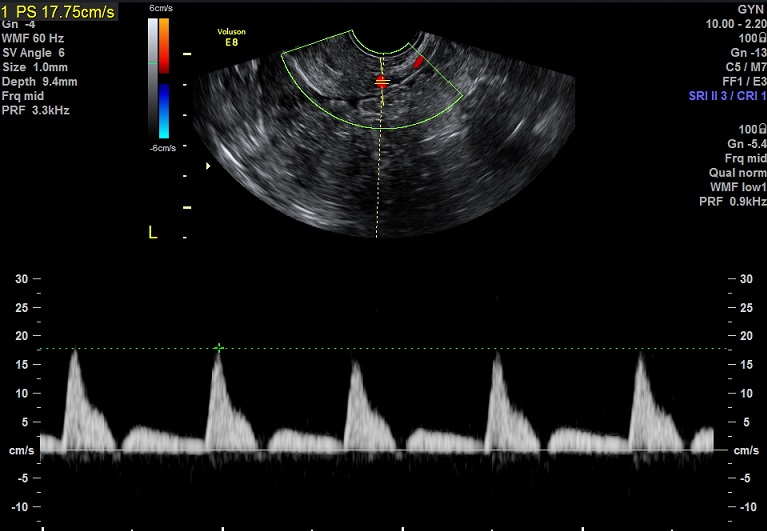

子宫动脉:

L:PSV:16.2cm/s EDV:2.0cm/s RI:0.88 S/D:8.0 PI:3.0,舒张早期血流缺失

R: PSV:33.7cm/s EDV:2.6cm/s RI:0.92 S/D:13.5 PI:3.95,舒张早期血流反向